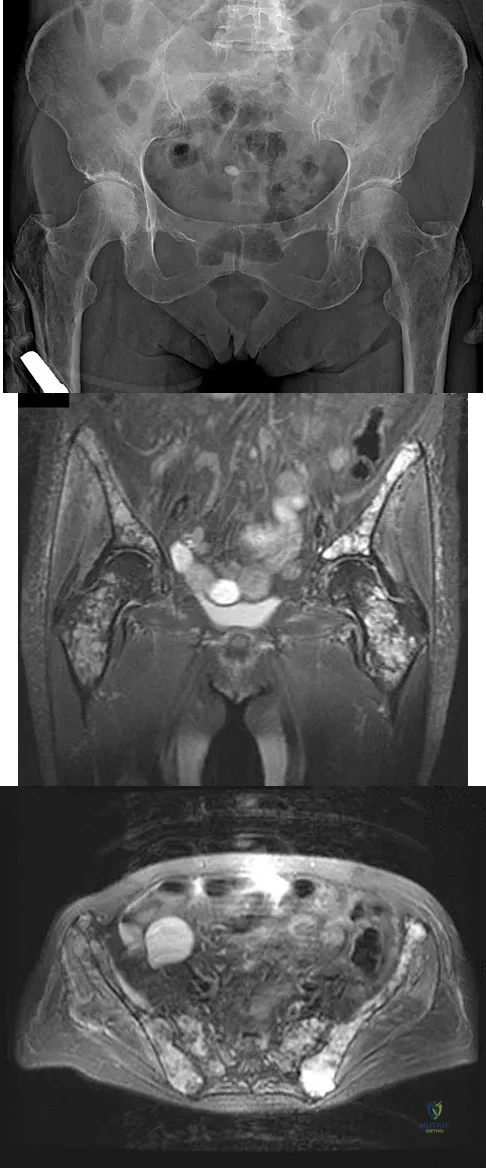

A 62-year-old woman reports diffuse aches and pains of the hip and pelvis. She denies any significant trauma but does have a history of chronic anemia. Figure 17a shows a radiograph of the pelvis, and Figures 17b and 17c show T2-weighted MRI scans. What is the most likely diagnosis?

Explanation